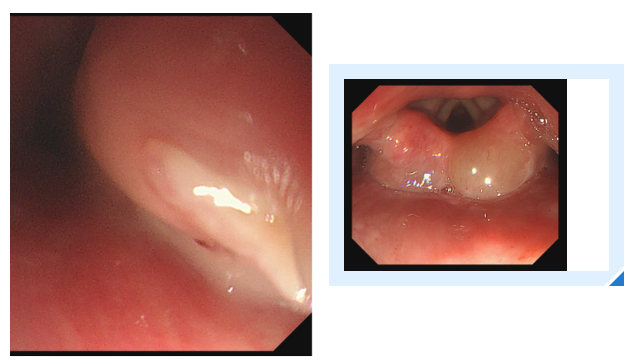

这时,消化内科主任吕后宁大夫有了一个大胆的想法:对透明帽进行改良。说干就干,吕主任迅速行动起来。他利用现有材料,经过一番巧妙的改造,一个特制的内镜透明帽应运而生。这个小小的豁口,就像是在透明帽上打开了一个“操作窗口”,为异物钳的操作预留了空间。

一切准备就绪后,医生再次为陈女士进行内镜操作。胃镜带着改良后的透明帽缓缓进入食管入口,当鱼刺出现在视野中时,吕主任轻轻旋转胃镜角度,将透明帽的豁口精准对准鱼刺嵌顿的位置。随后缓慢推送胃镜,让鱼刺的一部分稳稳地进入豁口内——此时豁口如同一个“固定卡槽”,将鱼刺牢牢固定住。

紧接着,异物钳从内镜通道中缓缓伸出,借助豁口提供的充足空间,异物钳以最佳角度顺利接近鱼刺,精准地夹住了鱼刺。医生确认夹持牢固后,保持异物钳与胃镜轴线平行,缓慢退镜。退镜过程中,透明帽始终包裹着鱼刺,有效避免了鱼刺尖端划伤食管壁。当胃镜退出口腔时,那根让陈女士痛苦不已的鱼刺被完整取出。